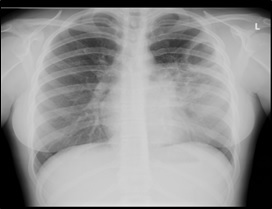

O estudo laboratorial revelou hemoleucograma normal e valores elevados de proteína C reactiva e velocidade de sedimentação. A radiografia do tórax evidenciou uma imagem hiperlucente arredondada associada a área hipotransparente no lobo pulmonar superior esquerdo (Figura 1). Foi efetuada tomografia computorizada pulmonar que confirmou lesão cavitada no lobo superior do pulmão esquerdo, medindo cerca de 50mm de maior eixo, associada a área de consolidação pulmonar (Figura 2), sendo a imagem compatível com infeção respiratória, nomeadamente, micobacteriose – tuberculose pulmonar (TP) e, posteriormente, confirmada por exame directo e cultural de expectoração.